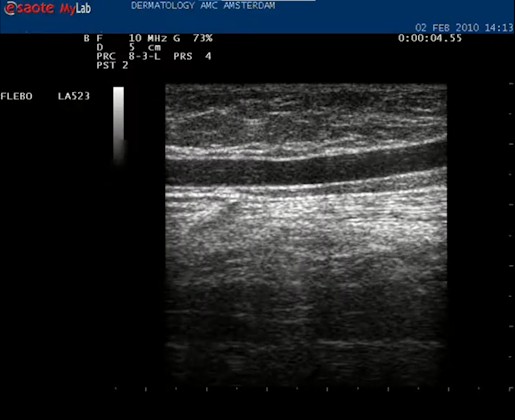

| Stamvaricose van de vena saphena magna | Esaote Mylab duplex |

| Met de echokop dwars op de binnenkant van het bovenbeen wordt direct een hooggelegen (extrafasciaal gelegen) vena saphena magna gezien. De VSM wordt in het midden van het beeld geplaatst. |

| Daarna de echokop draaien in de lengte richting van het vat. Nu is het mooi helemaal in beeld. |